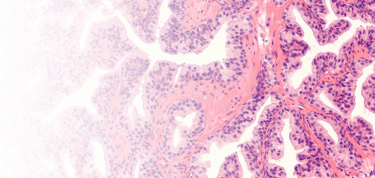

Our Anatomic Pathology workflow and AI platform was developed to provide pathology practices with a comprehensive digital pathology platform.

Techcyte Fusion AP is a comprehensive digital pathology platform that brings together all the stakeholders, use cases, patient information, and technology by digitizing those workflows and enabling the use of AI to increase the efficiency and accuracy of a pathology practice.

Techcyte does the hard work of integrating the EHR, LIS, PACS/VNA, scanners, storage, stain ordering, annotations, AI, messaging, worklist and reporting into an easy-to-use, modern, browser-based pathology workspace.